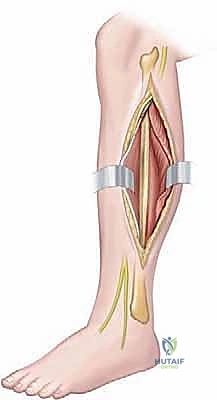

تُجرى العملية غالباً تحت التخدير الموضعي (إحصار العصب) أو التخدير النصفي، مع تخدير عام خفيف لراحة المريض. يتم استخدام عاصبة دموية (Tourniquet) لضمان رؤية جراحية خالية من النزيف.

2. الشق الجراحي (The Incision):

يُفضل الدكتور هطيف استخدام شق جراحي إنسي (Medial Approach) أو أخمصي (Plantar Approach) حسب موقع التمزق. يضمن هذا الشق الوصول المباشر إلى المركب الكبسولي مع الحفاظ على الأعصاب الحسية الدقيقة المحيطة بالإصبع.